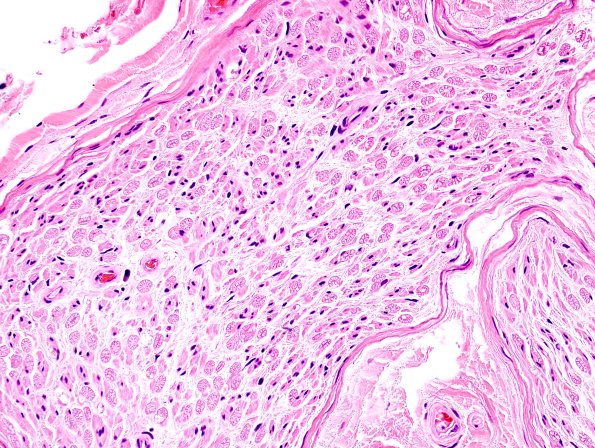

Washington University Experience | PERIPHERAL NEUROPATHY | 0 PNS ARTIFACTS | 5D Artifact, neurokeratin H&E 2

5D-F This pattern is designated as a “wagon wheel” appearance in cross sections in human (5D), monkey (5E) and Cheetah (5F); it is thought to represent autolysis. (H&E )